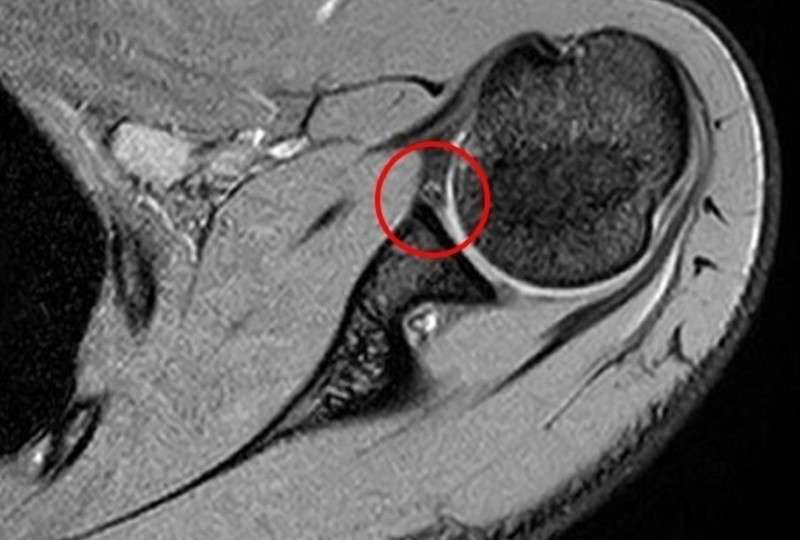

関節のMRI 第3版 | 上谷雅孝, 青木隆敏, 神島 保, 江原 茂, 杉本。肩関節のMRI−読影ポイントと新しい知見−第3版 | 佐志 隆士。その他検査(関節・軟骨) 肩MRI | AIC八重洲クリニック。ホテイ やきとり缶詰 岩下の新生姜入りしょうが味 70g×9缶セット 非常食。【裁断済】\r肩関節のMRI 改訂第3版\r佐志隆士、秋田恵一 編集\rメジカルビュー社\r\r・こちらで購入させて頂いたものです。\r・裁断済みです。そのため、状態は悪いとしています。\r 裁断済みの意味が分かる方のみ、ご購入をお願いいたします。\r・書き込み、マーカーはないと思いますが、確認漏れがあった場合はご容赦ください。\r・スキャン後ですので、多少のヨレやローラー痕がある可能性があります。ご理解の上ご購入をお願いいたします。\r・即購入OKです。\r 恐れ入りますが、値下げ交渉はご遠慮下さい。。肩関節脱臼に対する治療 | 長野整形外科クリニック。その他検査(関節・軟骨) 肩MRI | AIC八重洲クリニック。m3電子書籍 | 関節外科 2022年11月号 Vol.41 No.11 腱板断裂治療。肩関節疾患 | ならやまと整形外科 スポーツクリニック。肩関節(MRI): 正常解剖学 | e-Anatomy。肩関節脱臼|SPORTS MEDICINE LIBRARY|ザムスト(ZAMST)。Open Bore 3T MRIと320列面検出器CTの最新臨床応用 Toshiba 3T。肩関節(MRI): 正常解剖学 | e-Anatomy。プライマリケア医にとってMRIは、確定診断をサポートするための